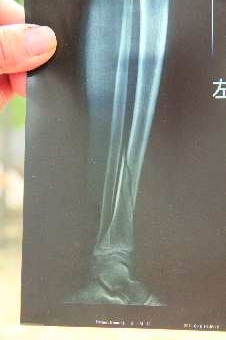

宋诗文的左腿腿骨CT片

因为午休时不遵守学校的纪律,在苍山县志成学校读五年级的12岁男童宋诗文的左腿被老师打成骨折。图为左腿打着石膏的宋诗文躺在家里养伤。 本报记者 张斌 王晓 摄